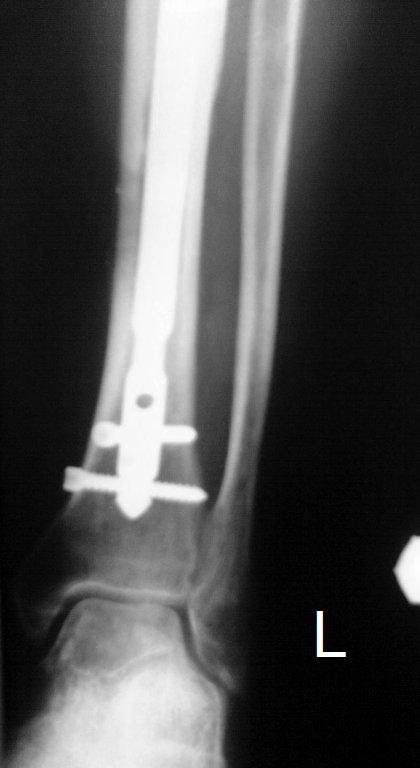

Итак, в настоящий момент больной пришел к нам с полной нагрузкой на оперированную конечность и с такой картиной

(см. приложение). Участок мягких тканей, с передней стенкой  нижней трети ББК, выгнил и представляет дефект

2×2,5 см. На перевязке - циркулярный(?) некроз костной трубки.

Имя     : tibLAT01.JPG

Тип     : image/jpeg

Размер  : 31351 байтов

Описание: отсутствует

Url     : http://weborto.net:8080/pipermail/ortho/attachments/20091123/dddb0a2c/attachment-0012.jpeg